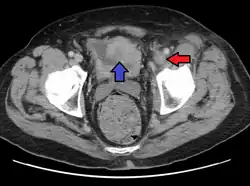

Tomografia komputerowa raka pęcherza moczowego. Guz oznaczony niebieską strzałką, czerwoną strzałką oznaczono zakrzepicę lewej żyły biodrowej zewnętrznej

Rak pęcherza moczowego oznaczony strzałką

Tomografia komputerowa

Tomografia komputerowa (TK) jest podstawowym badaniem obrazowym służącym do oceny zaawansowania raka pęcherza moczowego[153][154]. Tomografia komputerowa pozwala na dobrą dokładność diagnostyczną oceny obecności rozsiewu do narządów odległych i lokalnych węzłów chłonnych[153]. Czułość badania w zakresie rozpoznawania raka pęcherza moczowego jest oceniana na 85%, a swoistość 94%[155][154].

Nowotwór w zakresie pęcherza moczowego może być widoczny jako pogrubienie ściany narządu, które może ulegać wzmocnieniu kontrastowemu[156][157]. Badanie pomaga rozpoznać naciekanie tkanek okołopęcherzowych (T3), jednak nie umożliwia wiarygodnego rozróżnienia guzów nieinwazyjnych (Ta) od naciekających błonę mięśniową (T1)[158]. Ocena inwazji sąsiednich narządów (cecha T4) za pomocą TK może być trudna, szczególnie w przypadku podejrzenia nacieku pochwy i macicy, gdy oddzielająca je tkanka tłuszczowa jest cienka[156].